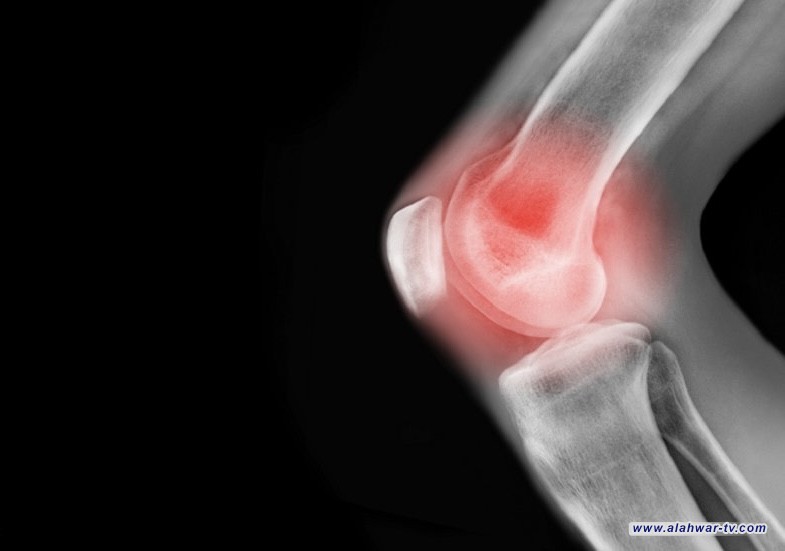

وتعرف هشاشة العظام بأنها مرض تنكسي يؤدي إلى تآكل الغضاريف التي تبطن أطراف العظام، ما يسبب الألم والتصلب وضعف الحركة، وحتى الآن، يقتصر العلاج على تخفيف الألم بالأدوية، وفي مراحل متقدمة، استبدال المفصل جراحيا.

وركز الباحثون على مرضى يعانون من هشاشة عظام خفيفة إلى متوسطة في الجزء الأوسط من الركبة، وهو الجانب الداخلي الذي يتحمل وزنا أكبر عادة.

وبعد عام، أظهر تصوير الرنين المغناطيسي أن مجموعة التدخل شهدت انخفاضا أكبر في الألم وتدهورا أبطأ لغضروف الركبة مقارنة بالمجموعة الضابطة.